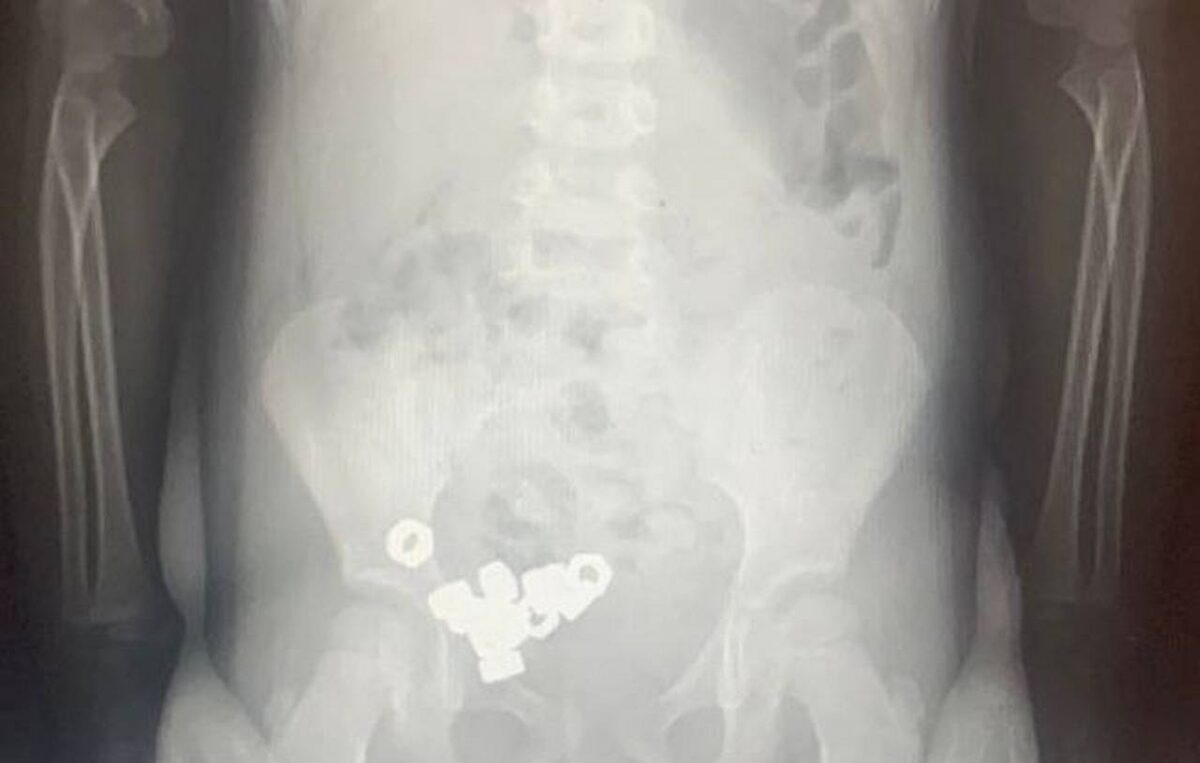

В Воронеже трехлетний мальчик проглотил стальных 16 гаек

Осмотр не выявил каких-либо специфичных симптомов, однако проведённый рентген органов живота зафиксировал присутствие множества контрастных теней (шестнадцать небольших гаечек) внутри пищеварительного тракта ребёнка, сообщили в региональном Минздраве.

Ребёнок был госпитализирован для постоянного мониторинга состояния ввиду потенциальной угрозы возникновения серьёзных последствий. Поскольку обнаруженные инородные объекты не обладали магнитными свойствами и не представляли собой химически агрессивные вещества, специалисты приняли решение о проведении консервативного лечения: рекомендована специальная диета, постельный режим, наблюдение за характером испражнений и периодическое проведение повторных рентгенологических исследований.

Спустя три дня абсолютно все попавшие внутрь малыша гайки благополучно покинули организм естественным образом, вследствие чего мальчик был отпущен домой.